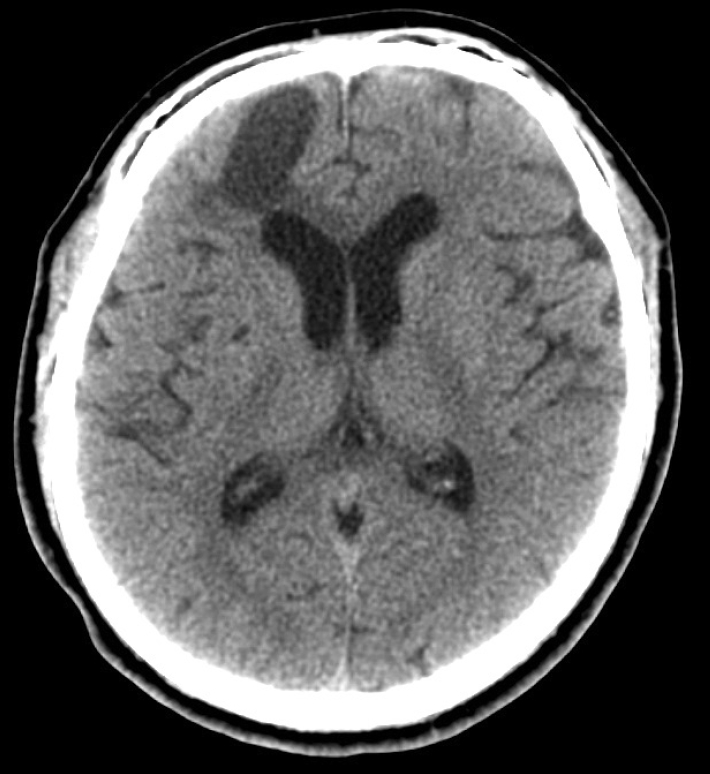

In the emergency room, he was found to be confused, but was following commands, and was oriented to person and place. On neurologic examination, his Glasgow Coma Scale score was 15. He showed normal pupillary reflexes, normal motor and sensory functions in all 4 extremities, normal deep tendon reflexes. A non-contrast CT scan of his brain was performed, and it showed significant air collection in the right frontal area and also a midline shift (Fig. 3). He was diagnosed with a tension pneumocephalus and referred to the neurosurgery department. Then, he underwent a bifrontal craniotomy for tension pneumocephalus. During the operation, we found adhesions between the nasal mucosa and dura mater, but there was no defect between nasal mucosa and dura and no CSF leakage. After detaching these adhesions, duroplasty and cranioplasty were performed. Postoperative conservative treatment was applied, including bed rest, meningitis prophylaxis, maintenance of extraventricular drainage. In the follow-up CT taken at 2 weeks after the surgery, resolution of tension pneumocephalus was observed (Fig. 4). His condition was stable and he showed a normal mental status, not confused. He was discharged 14 days after the surgery. In an endoscopic examination performed in the 2nd month, there was no skull base defect or CSF leakage (Fig. 5). The patient did not have any complaints or symptoms for 6 months after the surgery.